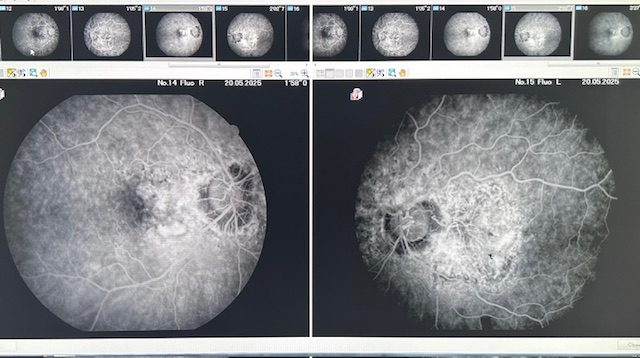

Fluoreszenzangiographie

Die Fluoreszenzangiographie ist ein wichtiges diagnostisches Verfahren, das von Augenärzten eingesetzt wird, um die Durchblutung der Netzhaut und der Blutgefäße im Auge zu beurteilen. Bei diesem Verfahren wird ein fluoreszierender Farbstoff in eine Vene injiziert, der entlang des Blutkreislaufs transportiert wird. Mit einer speziellen Kamera werden anschließend Bilder angefertigt, die die Verteilung des Farbstoffs im Auge zeigen. Dadurch können Erkrankungen wie diabetische Retinopathie, Makuladegeneration oder retinaler Gefäßverschluss frühzeitig erkannt und behandelt werden. Die Fluoreszenzangiographie ist ein unverzichtbares Werkzeug in der modernen Augenheilkunde, das dazu beiträgt, das Sehvermögen der Patienten zu bewahren und zu verbessern.